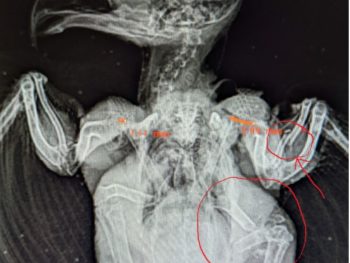

There ARE fates worse than death

My heart cracks a little more every time I see or hear the advice “Don’t take it to the rehabber! They’ll just kill it!” Or Don’t call animal control; they’ll just kill it; or don’t call the game warden, etc, etc. The idea that people who have careers and avocations dedicated to helping animals will […]